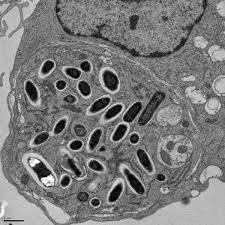

- 兩種型態

- Elementary body(EB): 傳播用

- Reticulate body(RB): 較大,細胞內生長繁殖

- Spore 注射進入細胞,青蛙下蛋、長出細胞膜,再炸一堆Spore